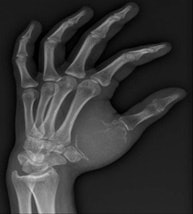

In the third year of my residency in 1982, I began to be attracted by the new way to perform interventions through percutaneous and endovascular approaches, and for a few months I went to the MD Anderson Center in Houston, Texas, U.S. There I took an important decision, which was that I would like to be completely involved in interventional radiology (IR), and with the great support of the CUN, this is what I have done for the rest of my professional life.